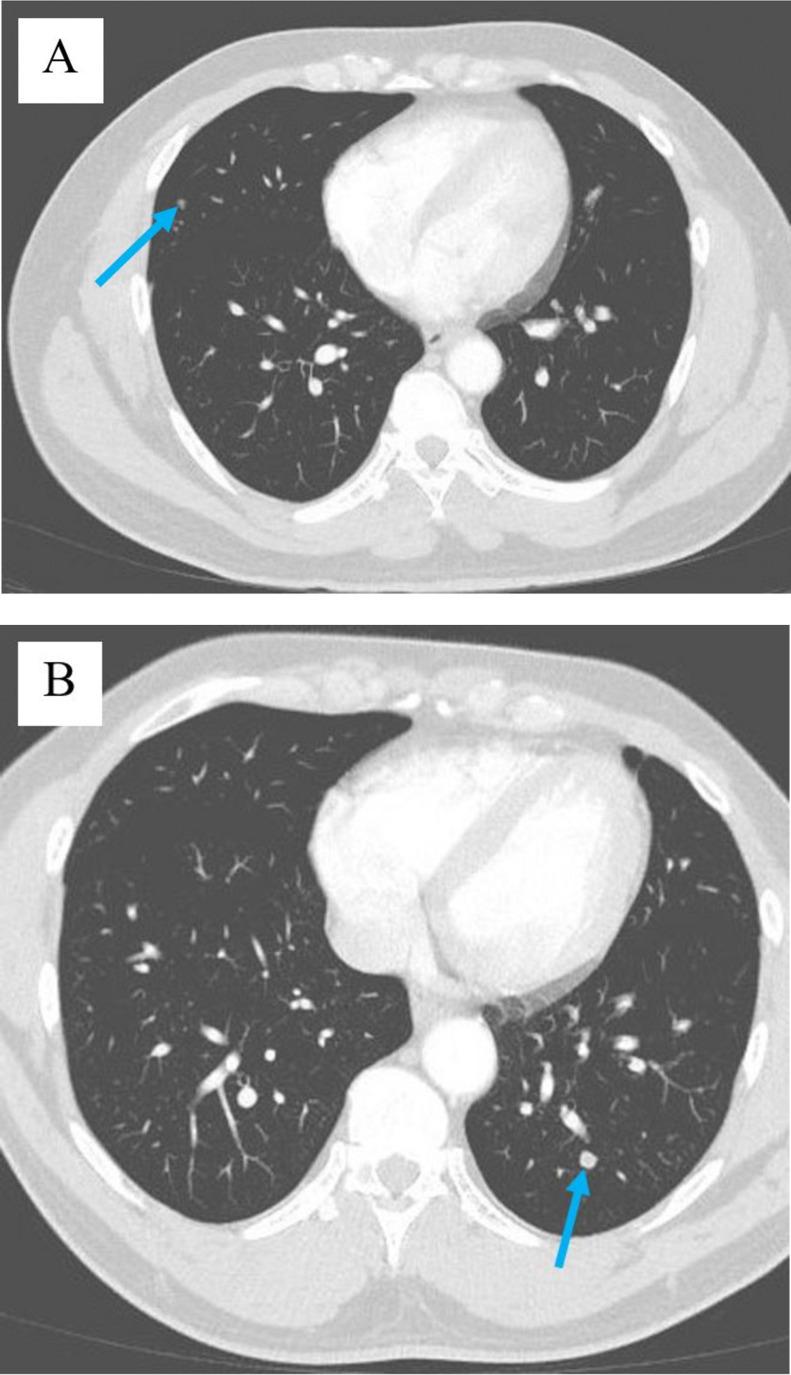

Paratesticular leiomyosarcoma is a rare malignant tumor deriving from the smooth muscle of structures surrounding the testes, including the epididymis or scrotum. With few cases of genitourinary soft tissue sarcomas reported in the literature, little is known about progression, management, and treatment. Herein, we report a case of metastatic paratesticular leiomyosarcoma in a 47-year-old male with no past urological history. The patient initially presented with a firm, painless right scrotal mass, and ultimately developed soft tissue and pulmonary metastases.

睾丸旁平滑肌肉瘤是一种罕见的恶性肿瘤,起源于睾丸周围结构(包括附睾或阴囊)的平滑肌。由于文献中报道的泌尿生殖系统软组织肉瘤病例较少,对于其进展、管理和治疗知之甚少。在此,我们报告一例47岁男性转移性睾丸旁平滑肌肉瘤病例,该患者既往无泌尿系统病史。患者最初表现为右侧阴囊质地坚硬、无痛性肿块,最终出现软组织和肺转移。